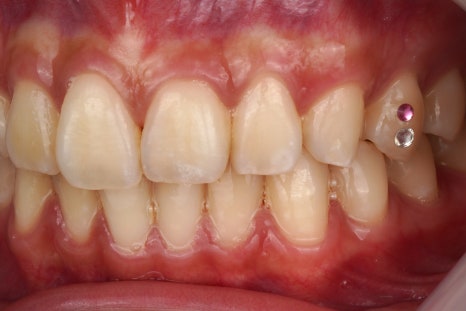

제거 전

제거 후

진짜 깨끗하게 떨어졌죠

그냥 뗀 게 아니라

치과용 기구를 이용해서 정확히 떼어내고

전문적인 앞니 치료 도구들을 활용해서

치아 표면을 활택하게 만듭니다.

어디에 접착제가 묻어있었고

어디에 투스젬이 있었는지

정말 감쪽같이 떨어지지 않았나요?